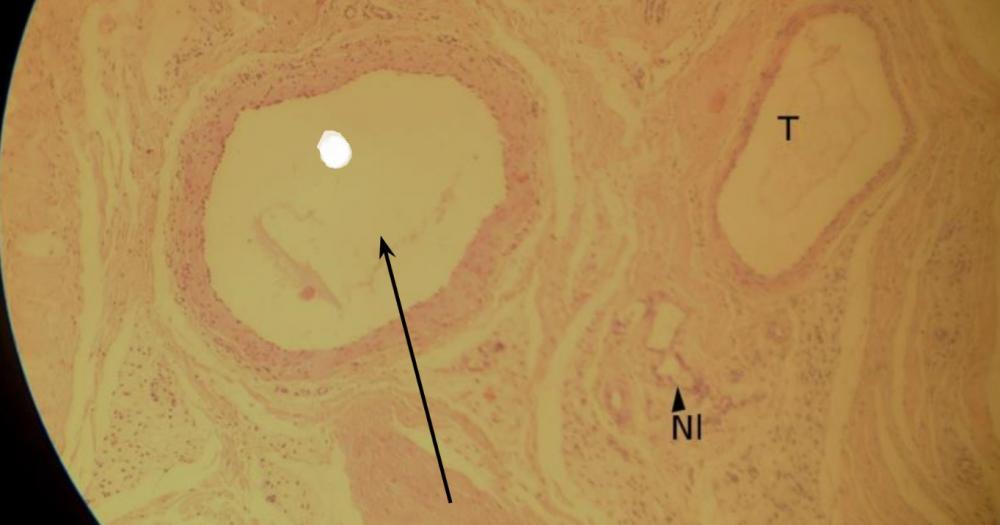

Pytanie 97

światło tętnicy (tętnica mięśniowa i żyła)

Pytanie 98

błona wewnętrzna tętnicy - nabłonek jednowarstwowy płaski (tętnica mięśniowa i żyła)